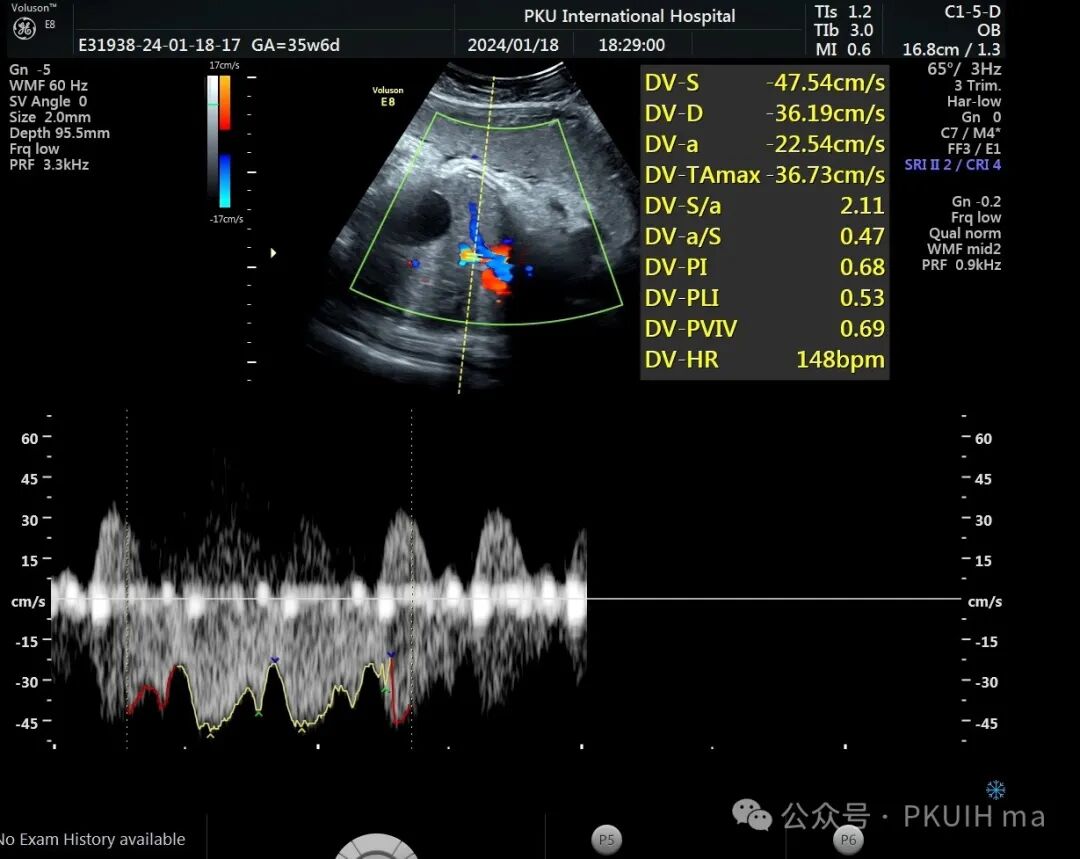

静脉导管血流阻力还可以,正常范围内。